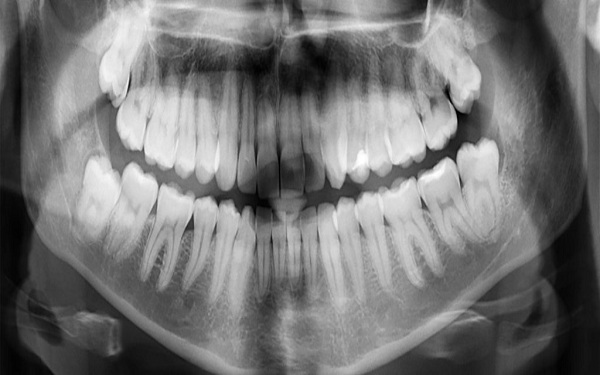

Tooth enamel is produced by a type of cell called an ameloblast. These secrete the proteins that form enamel while the tooth is still in the gum.

Unfortunately, once the process of forming tooth enamel is complete and the tooth has emerged, our ameloblasts die off. But we continue to lose enamel throughout our lifetime.

But once there’s a visible cavity on the tooth, it needs to be treated by a dentist – which usually means drilling, and packing the hole with a dental filling.

And for deep cavities that reach the dentine layer underneath the enamel, a filling would still likely be required.